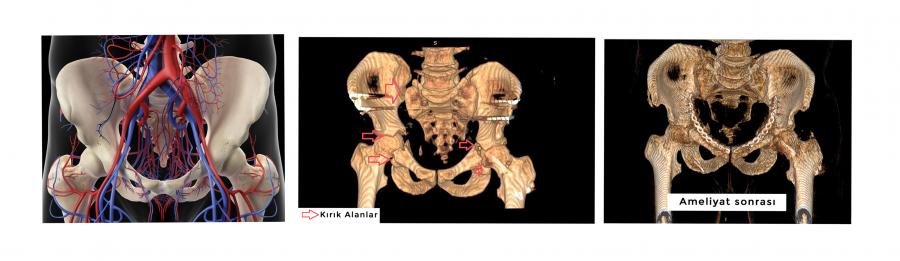

Araç içi trafik kazası geçiren 34 yaşında erkek hasta, Hastanemiz Acil Servisine getirildiğinde vücudunun farklı yerlerinde pek çok kırık mevcuttu. Hastanın kırıkları arasında pelvis (leğen) kemiğinde 7 farklı yerde parçalı kırıkları ve çıkığı da vardı. Hayati tehlikesi bulunan hasta ilk müdahalesi acil servis tarafından yapıldıktan sonra KTÜ Farabi Hastanesi’nde Dr. Öğretim Üyesi Kerim Öner tarafından operasyona alındı. Altı saat süren başarılı bir operasyon ile leğen kemiğine 3 farklı noktadan yapılan girişim ile kırıkları ve çıkıkları tespit edilerek hayati riski ortadan kaldırıldı. Daha sonrasında devam eden tedavilerle hasta sağlığına kavuştu.

Pelvis kırıkları, yüksekten düşme trafik kazaları gibi yüksek enerjili yaralanmaAlar sonucunda görülmekte olup hayati tehlike içermektedir. Pelvis kırıkları vücudun diğer bölge kırıklarından farklı olarak bağırsaklar ve mesane gibi karın içi organların bulunduğu ve birçok hayati önem arz eden damar ve sinirlerin geçtiği bir bölge olması sebebi ile kritik öneme sahiptir. Bu nedenle pelvis cerrahisi deneyimli bir ekip ile tam donanımlı hastanelerde yapılmalıdır. Ülkemizde sayılı merkezde yapılan pelvis cerrahisi bölgemizde Karadeniz Teknik Üniversitesi Farabi Hastanesi’nde başarı ile gerçekleştirilmektedir.